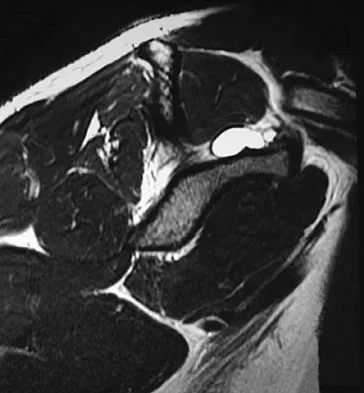

A 72-year-old woman who fell on her right shoulder while using a treadmill is now unable to elevate her right arm. An MRI scan is shown in Figure 7. What is the most likely diagnosis?

Explanation

The MRI scan reveals a large chronic rotator cuff tear with retraction and fatty infiltration atrophy of the supraspinatus and infraspinatus tendons. This tear is responsible for the patient's severe weakness and inability to elevate the arm.